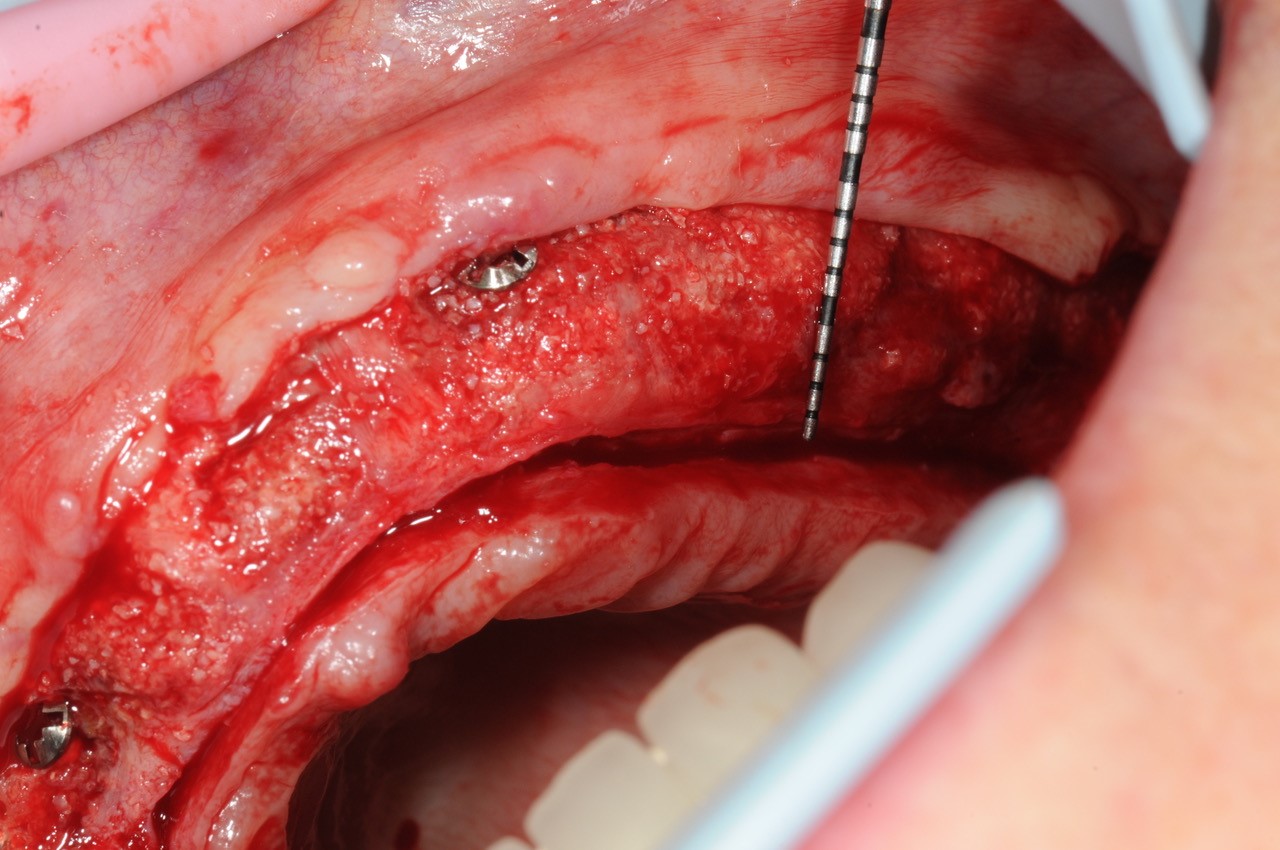

Block augmentation with maxgraft® in the maxilla - PD Dr. Dr. F. Kloss

Initial situation - bone defect in maxilla after loosing right canine